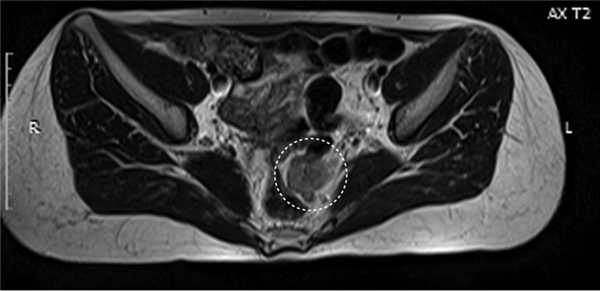

С марта 2007 г. по август 2009 г. больной проведено 6 лапароскопических вмешательств — флюоресцентная ревизия, множественная биопсия брюшины и интраоперационная ФТД. Во всех случаях использовали фотосенсибилизатор фотогем, вводимый внутривенно за 48 ч до операции. Использовали цилиндрический диффузор с экранирующим устройством — трансдьюсер. Последовательно облучали доступные отделы париетальной брюшины: 20 позиций по 2 мин. Мощность лазера 600 мВт, плотность энергии 6 Дж/см 2 . В 2 случаях стандартную методику дополняли проведением ФДТ в жидкой среде после заполнения брюшной полости 4 л изотонического раствора натрия хлорида. Начиная с 7-й лапароскопии при ревизии и биопсии микроочаги мезотелиомы не выявлялись. При обследовании в апреле 2010 г. больной выполнено КТ и УЗИ брюшной полости и малого таза, а также МРТ, при которой обнаружили опухолевые узлы в области ректосигмоидного и верхнеампулярного отделов толстой кишки (рис. 2). Рис. 2. Опухолевый узел в мезоректальной клетчатке.